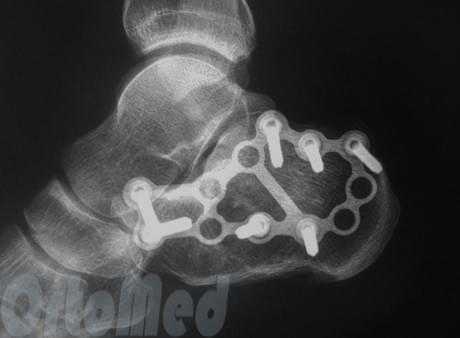

Пациент М. 1980 г.р., травму получил при падении на стопы с высоты 1,5 метра. Лечился по месту жительства (в травмпункте районной больницы) консервативно в гипсовой повязке в течение 14 дней. Консультирован в травматологическом отделении ФГБУ «УНИИТО им. В.Д. Чаклина» Минздрава РФ, предложено оперативное лечение. При поступлении кожные покровы стопы чистые, без признаков воспаления и сдавления тканей. Стопа отечна, уплощена. На рис. 1 представлены рентгенограммы пациента. Прооперирован через 2 недели после травмы. Операция состоит из двух этапов. Первый этап заключается в наложении дистракционного аппарата. Проводятся две спицы 1,8 мм во фронтальной плоскости: первая через нижнюю треть диафиза большеберцовой кости, вторая через бугор пяточной кости (рис. 2). Спицы фиксируются в дистракционном аппарате, выполненном из двух полуколец, соединенных между собой двумя телескопическими тягами. Особое расположение полуколец, фиксация спиц на концах полуколец, крепление кронштейнов для телескопических тяг обеспечивает тракцию пяточной кости в необходимом направлении с использованием минимального количества спиц и внешних опор при сохранении необходимого поля обзора для проведения рентгенологического и визуального контроля репозиции и фиксации. Второй этап - закрытая элевация импрессированной суставной поверхности и окончательная репозиция пяточной кости. Через разрез длиной до 1 см по латеральному краю ахиллова сухожилия (рис. 3) в месте его прикрепления к пяточной кости под соответствующий фрагмент подводится элеватор (рис. 4), манипуляцией которым устраняется смещение и выполняется провизорная фиксация спицами 1,5 мм (рис. 5). При сагиттальном раскалывании суставной фасетки целесообразно проведение одного-двух винтов субхондрально (рис. 6). Стержень вводится с дорзальной поверхности пяточной кости по ее оси через разрез до 2 см по предварительно сформированному остеотомом каналу (рис. 7, 8). Далее через проколы кожи с помощью кондуктора (рис. 9) выполняется запирание винтами с латеральной поверхности, внешнее устройство демонтируется. Достигнуто удовлетворительное стояние отломков (рис. 10).

Рис. 10. На рентгенограмме левой стопы в прямой и боковой проекциях определяется удовлетворительное стояние костных фрагментов на фоне металлофиксатора